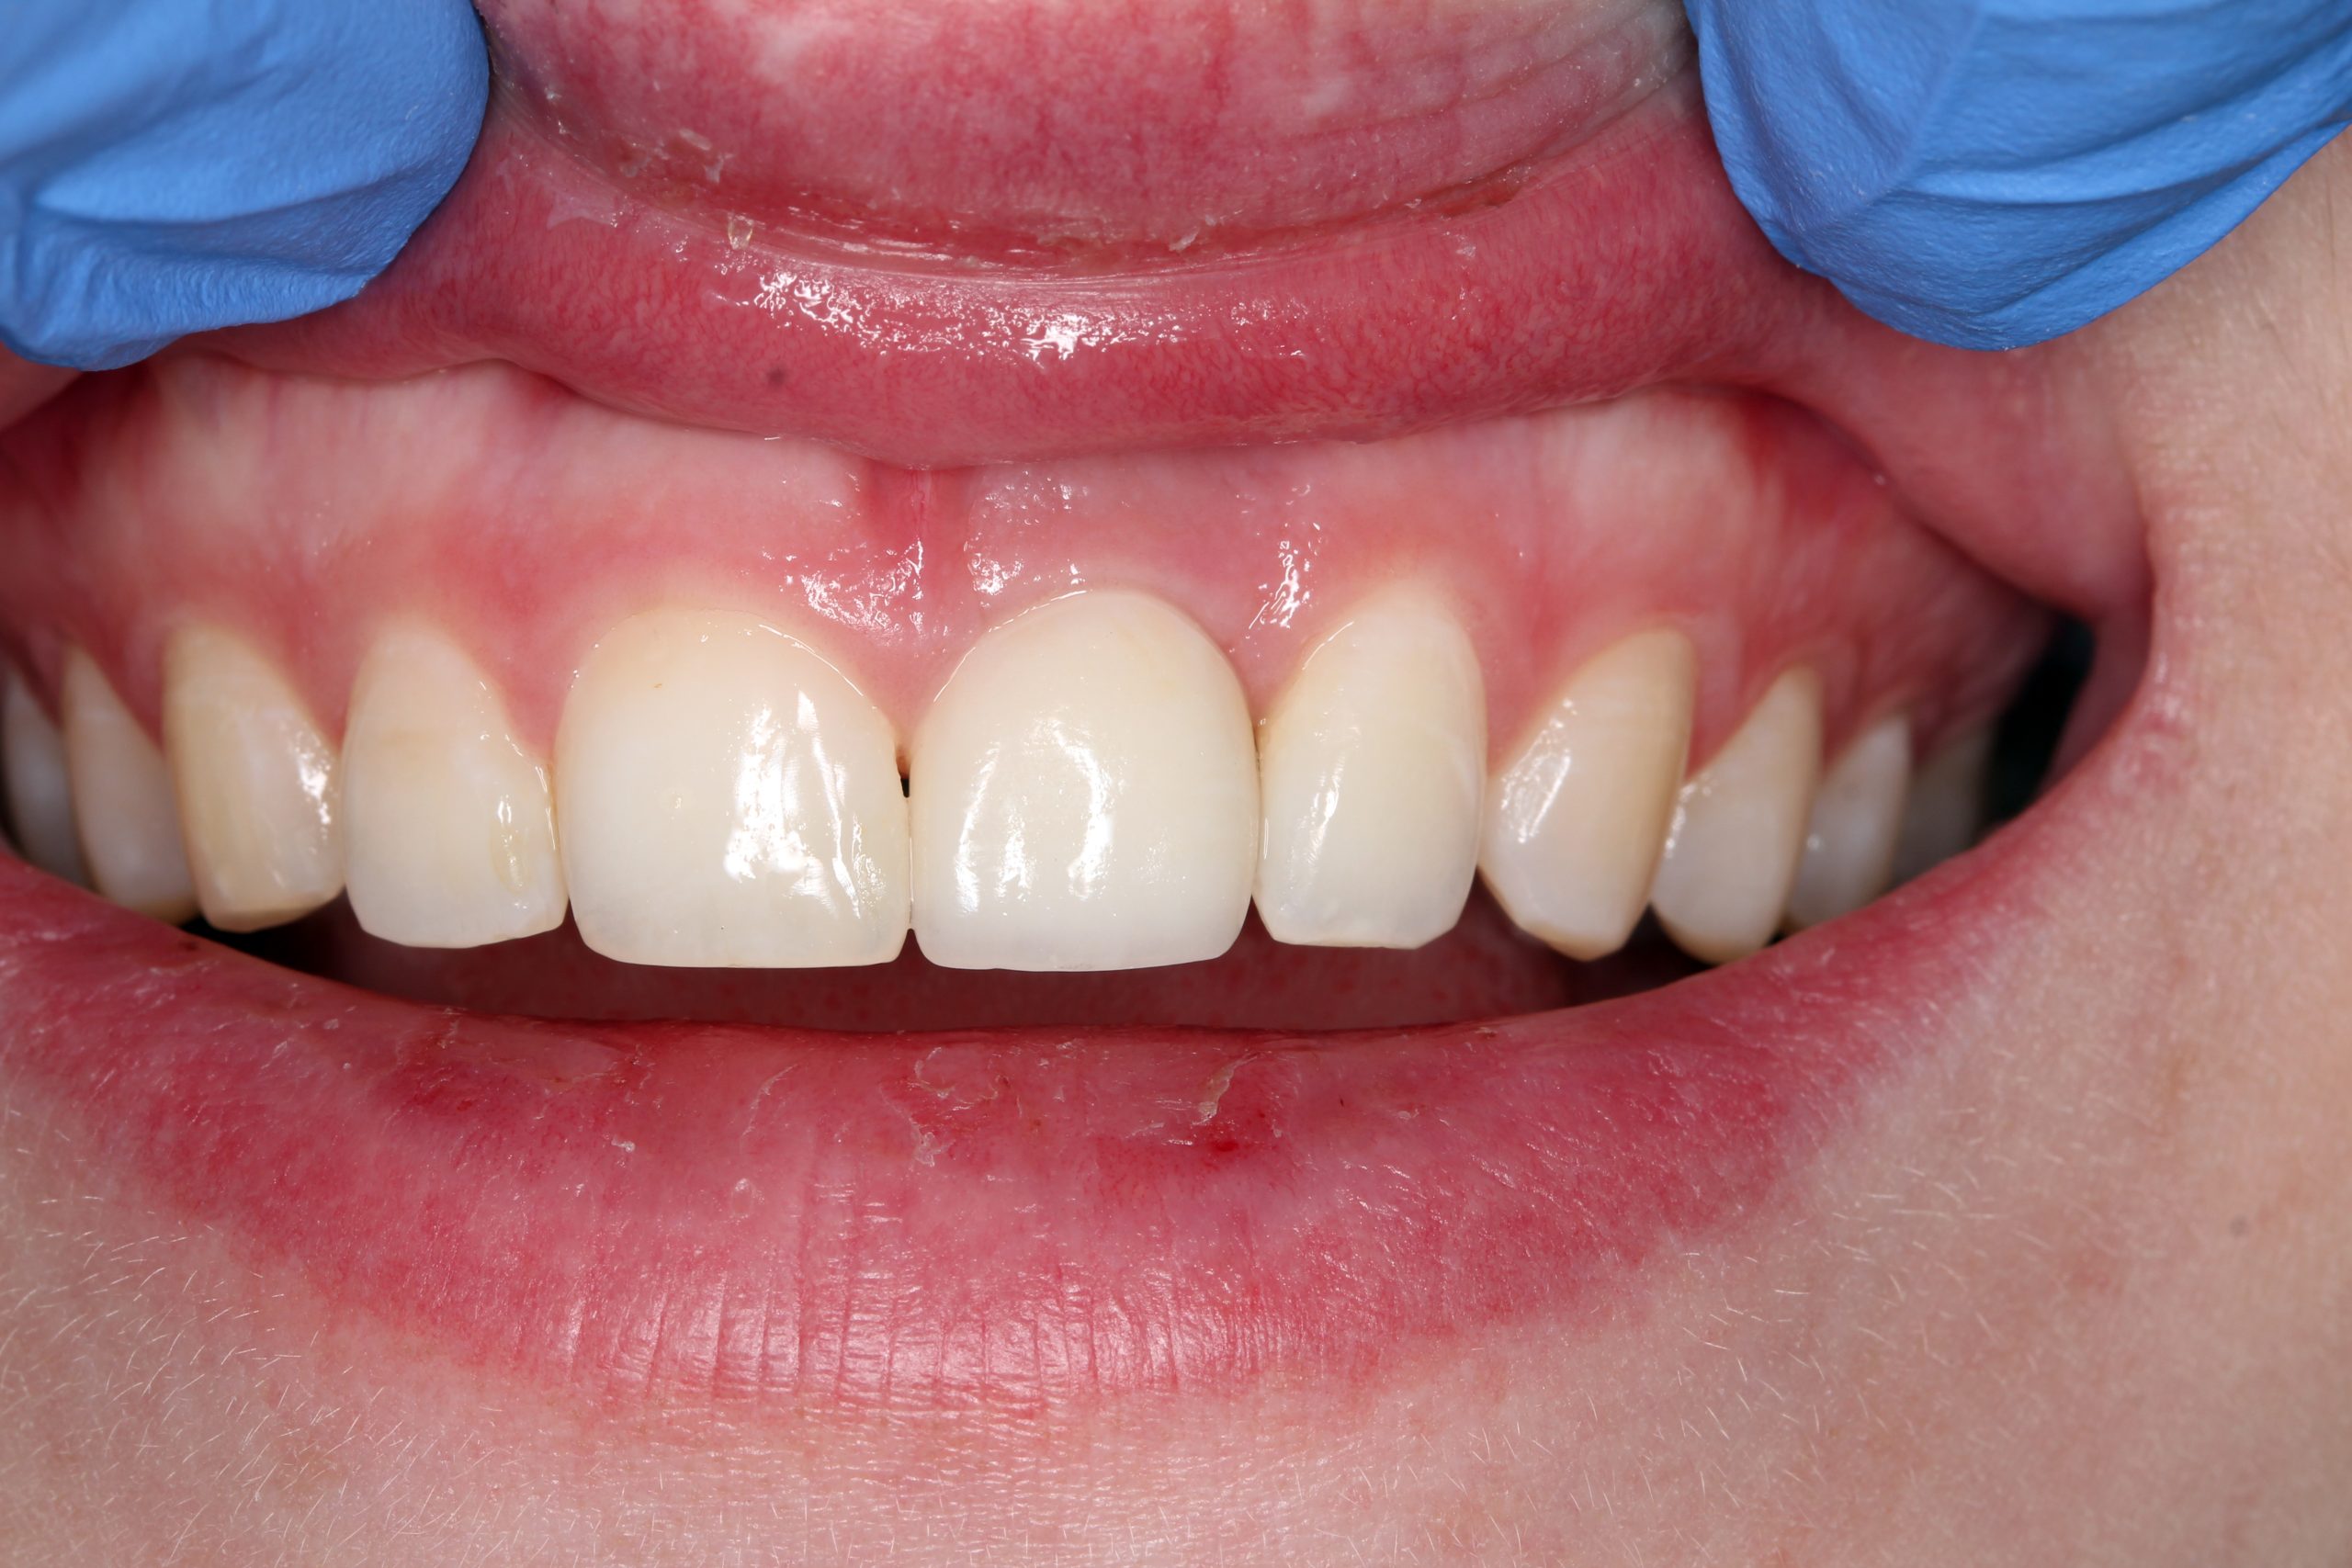

The patient‘s smile at the recall after three years. Minimally invasive surgical procedures and preservation of the surrounding tissue made it possible to achieve the best possible esthetic and functional result.

The X-ray after three years also shows a healed socket without resorptive changes.